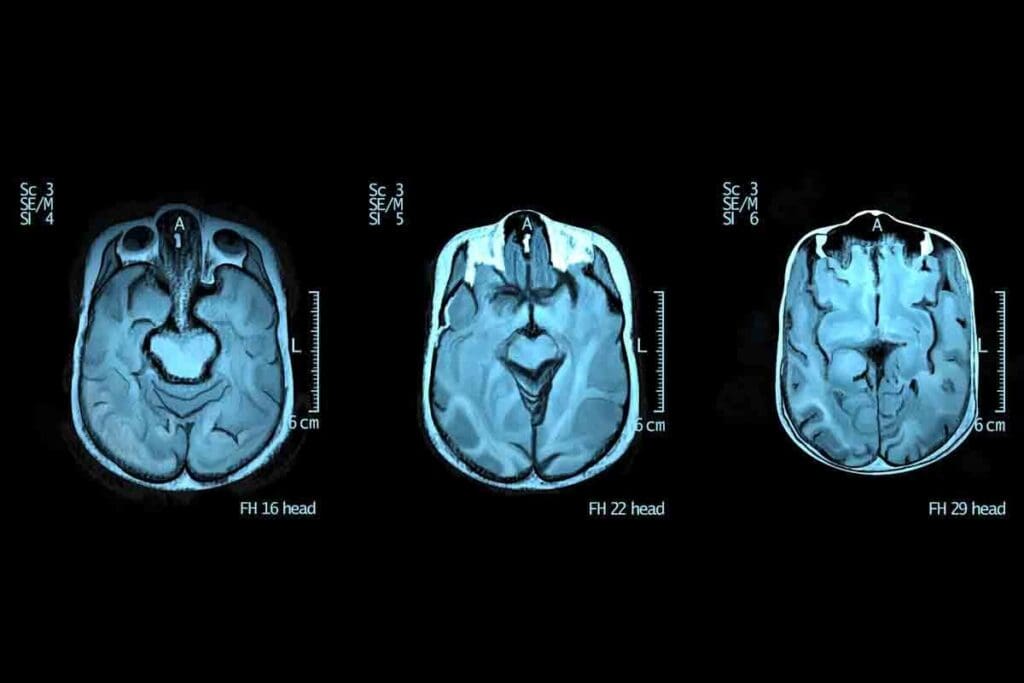

Diagnostic Tests for Brain Tumors

Tests are key to finding brain tumors. They include:

- Imaging tests like MRI and CT scans, which show brain details.